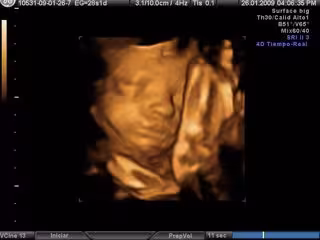

Archivo - Ecografía en una foto de archivo de Europa Press.

Archivo - Ecografía en una foto de archivo de Europa Press. - EUROPA PRESS - Archivo